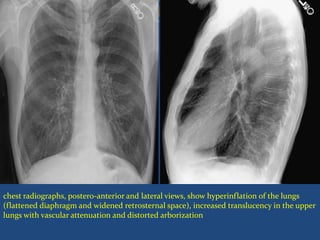

Main radiological sign :

 Hyperinflation of lung

 Decrease pulmonary vascularity peripherally

Retrosterrnal air space depth

Heart appears long and narrow

 `Barrel chest'

chest radiographs, postero-anterior and lateral views, show hyperinflation of the lungs

(flattened diaphragm and widened retrosternal space), increased translucency in the upper

lungs with vascular attenuation and distorted arborization

Main radiological sign:  Hyperinflation of lung  Decrease pulmonary vascularity peripherally Retrosterrnal air space depth Heart appears long and narrow  `Barrel chest'

chest radiographs, postero-anteriorand lateral views, show hyperinflation of the lungs (flattened diaphragm and widened retrosternal space), increased translucency in the upper lungs with vascular attenuation and distorted arborization